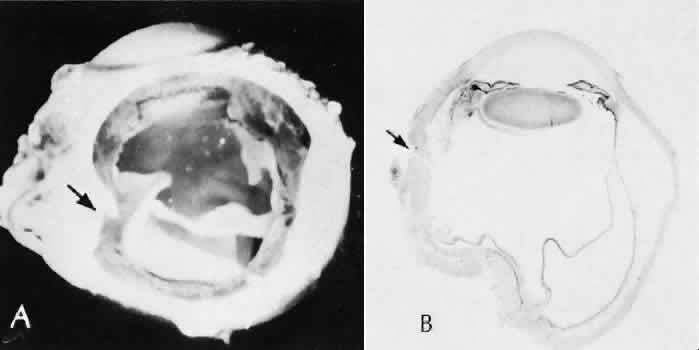

| Successful wound healing in the eye is a precise, ordered series of events